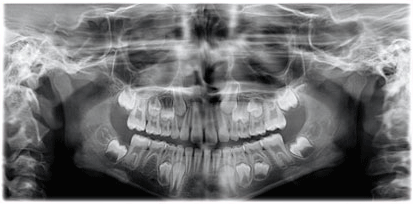

Panoramic imaging

Standard panoramic program.